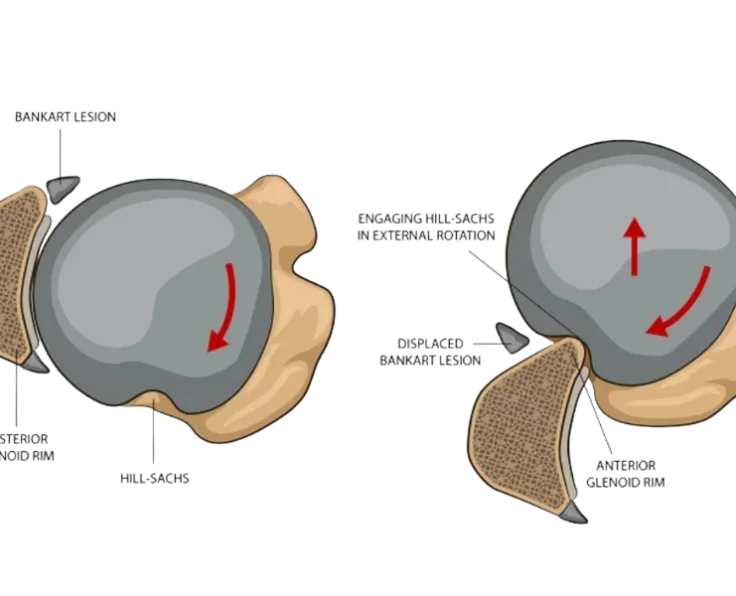

Bankart Repair

A Bankart Repair is a treatment that is used to avoid recurrent anterior shoulder dislocations caused by instability in the shoulder's rear.

Remplissage

When combined with arthroscopic Bankart repair, the Remplissage approach has been shown to reduce the frequency of recurrent anterior shoulder instability.